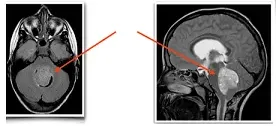

后面的3个月,儿子的症状时好时坏,但我意识到不对劲是有天看他走路跌跌撞撞的,像踩在棉花上一样。我赶紧给爱人打电话,他还在出差,我就先带着儿子到医院检查。眼科检查做了,说是视神经乳头水肿,直到核磁出来,我才觉得天一下子塌了:脑干上这么大一个肿瘤,让我的心瞬间凉透了。